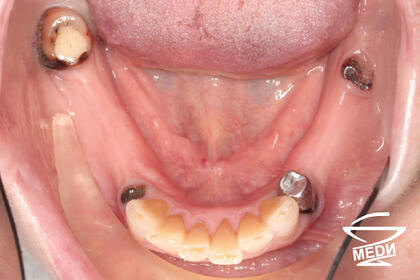

Причины обращения: жалобы на дискомфорт при пользовании съёмными протезами, плохую фиксацию протезов.

До начала лечения

После лечения лечения